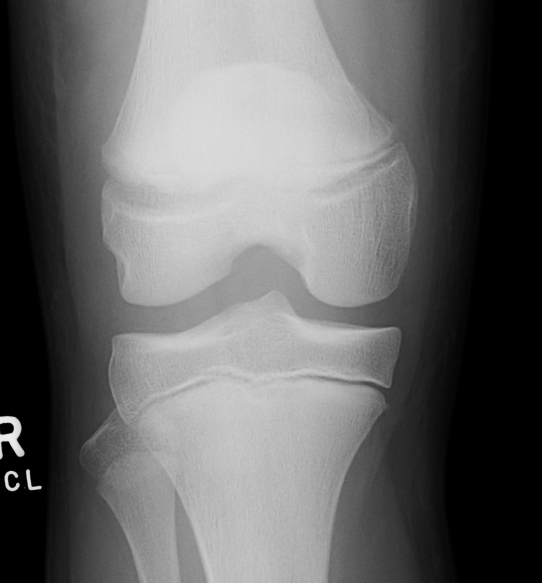

Salter Harris I

Salter Harris II